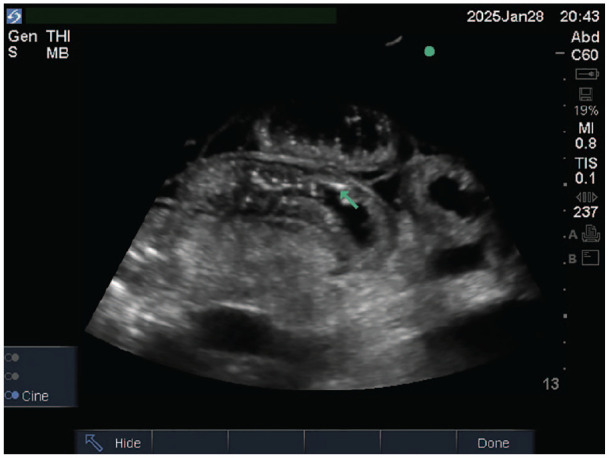

Pneumatosis intestinalis (PI) is characterized by the presence of air within the walls of the small intestine, large intestine, and sometimes the gastric wall. The mechanism and pathogenesis of PI are poorly understood. The discovery of PI can occur in the form of an incidental finding, such as a benign course or a life-threatening condition, such as intestinal ischemia. Point-of-care ultrasonography (POCUS) for pneumatosis intestinalis (PI) is rarely reported in adults, with only 1 previous poster presentation. However, POCUS is well-documented in the pediatric population, particularly for the diagnosis of intussusception. We present a 78-year-old man with longstanding uncorrected severe pulmonary stenosis, right-sided heart failure, atrial fibrillation on dabigatran, diabetes, and cirrhosis who presented with progressive abdominal distension. POCUS and computerized tomography of the abdomen showed ascites, diffusing small-bowel wall thickening with edema, and pneumatosis intestinalis, without portal venous gas or vascular occlusion. Patient was transitioned to palliative care on diuretics, lactulose; follow-up ultrasound showed only mild ascites but persistent small-bowel PI. This case report marks the second instance of POCUS being utilized for PI in an adult population. POCUS can play an essential diagnostic role at the bedside, ruling out serious underlying etiologies and guiding physicians in further diagnostic testing.